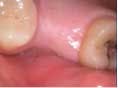

Case 2: Lateral wall sinus osteotomy with block grafting and platelet-rich fibrin (PRF)

An 81-year-old female with stent placement 10 years ago taking no medications presented with a chief complaint that her old prosthesis broke, and she cannot chew and function. She had a previous bridge consisting of an implant in the No. 1 site combined with the natural teeth and implants in the 8, 9, 14, 15. No. 8, 9 implants were malpositioned with a 35-degree angle and significant mucogingival defects.

Under local anesthesia, a full thickness flap was elevated from the upper right to upper left posterior segments. Using a piezoelectric handpiece, a buccal window hinge osteotomy was elevated in the maxillary right posterior region. A mixture of DFDBA, anorganic bovine bone, and PRF was placed. A collagen membrane was used to cover the buccal window. Simultaneously, two puros J-block allografts were secured in the 5 to 7 and 10 to 12 region with stainless steel screws (1.6 x 8 mm screws). A mixture of DFDBA, anorganic bovine bone and PRF was placed over each area and covered with PRF sheet and a collagen membrane. Primary closure was obtained with CV-5 Goretex sutures. Healing was uneventful. After six months of healing, six straight implants were placed in sites 3, 4, 5, 6, 11, and 12. Healing abutments were placed at stage I. Healing was uneventful. After four months of healing, six custom abutments were fabricated by his dentist and cover screws were placed on implants 8 and 9 and converted into pontics.

Removing the implants would have created a large buccal defect, which would have created elongated pontics in the maxillary anterior region. The prosthesis was completed, and the patient is stable and highly appreciative of her ability to smile and chew.

Case 2: Sinus lift, bone graft, PRP, and after healing implant placement